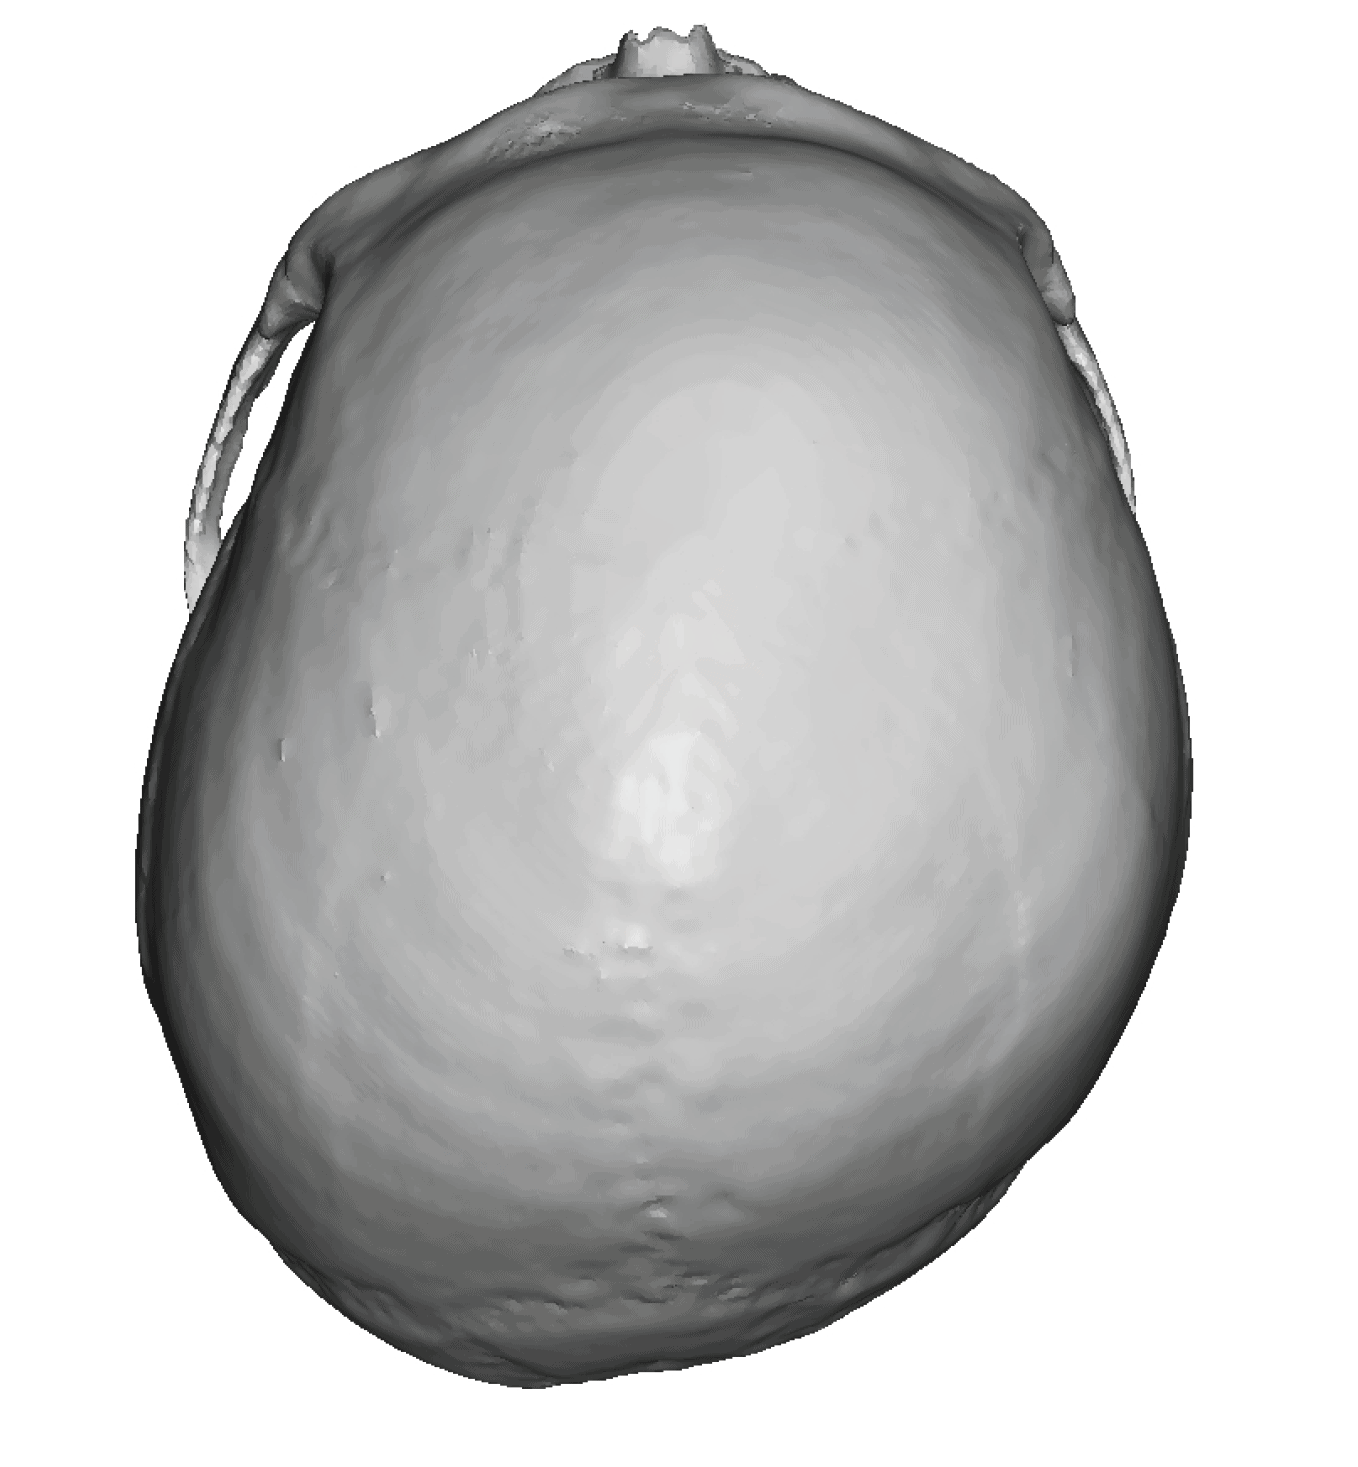

Patient 28

Desire for rounder shape to the top of the head from a congenital parasagittal deficiency skull shape.

Custom skull implant designed to fill in the parasagittal deficiencies.

Desire for rounder shape to the top of the head from a congenital parasagittal deficiency skull shape.

Custom skull implant designed to fill in the parasagittal deficiencies.